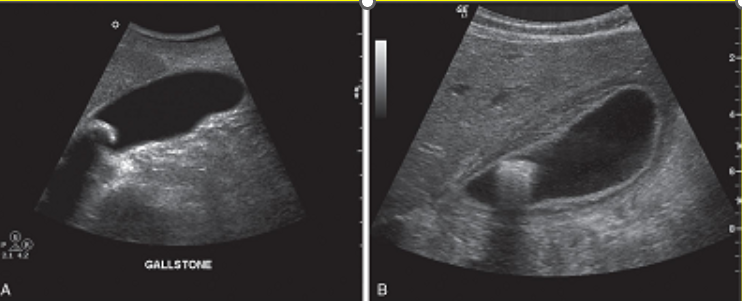

A single large gallstone near the neck of the gallbladder.